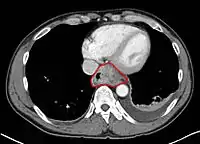

- Middle thoracic esophagus:

- Lower border of the azygos vein to the inferior pulmonary veins

- By endoscopy, 25 to <30 cm